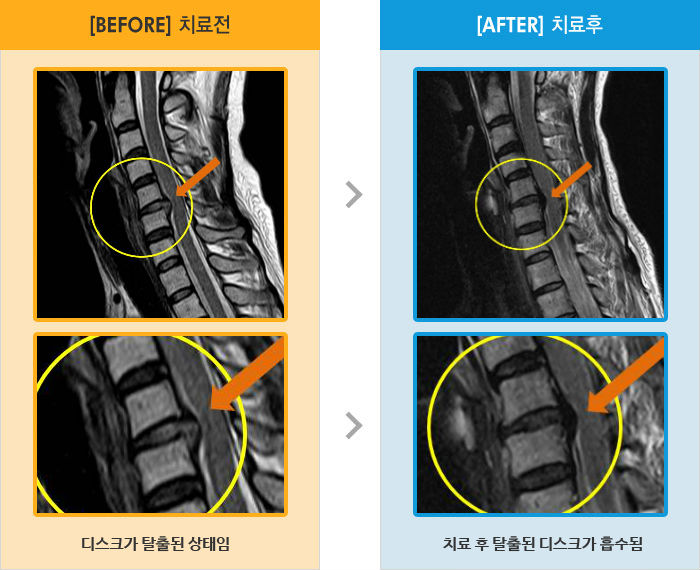

Before

After

목과 왼쪽 팔에서 1,2번째 손가락까지 저리고 당기는 통증

2012.05.07 ~ 2013.03.13

Before

After

허리와 양쪽 엉덩이 통증 및 좌측 둔부, 대퇴, 소퇴 후면부 통증 및 저림

2013.05.14 ~ 2014.04.23

Before

After

목 통증 및 우측 팔 통증으로 위로 들 수 없는 상태

2017.01.05 ~ 2017.08.04

Before

After

목부터 양어깨 손가락까지 저림, 야간통

2015.05.13 ~ 2016.06.27